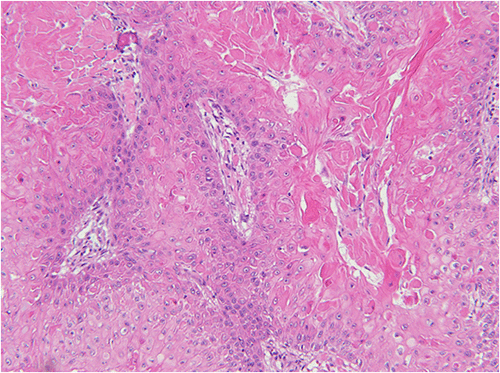

Figure 2. Histopathological Features of PTT. Published with Permission

A, 100x) Dense clusters of squamous cells characterize the PTT

B, 100x) Cystic regions with keratinization lacking a granular layer (arrow) and peripheral palisading of the basal layer are evident

C, 200x) Squamous cells with minimal cytologic atypia and abundant keratin are observed